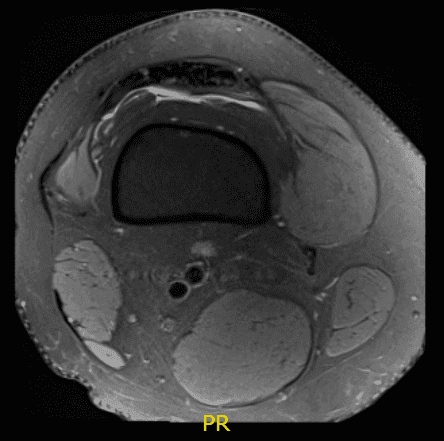

Resultado de la resonancia magnética recibido, hay estado tras la reconstrucción del ligamento cruzado anterior. El injerto está intacto. La formación de quistes tubulares está presente dentro del túnel tibial. Hay una gran desgarredura en forma de asa de cubo del menisco medial, desplazada hacia la muesca intercondilar y sobre el cuerno anterior.

Hay un diminuto remanente de cápsula en la parte posterior y periférica. El menisco lateral muestra deshilachamiento en el margen libre del cuerno posterior y la parte adyacente del cuerpo sin desgarro sustancial.